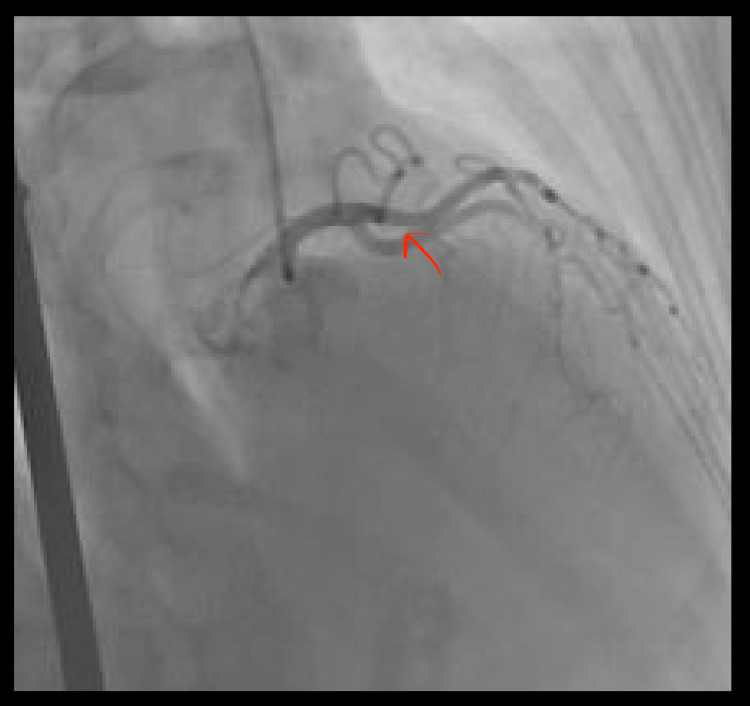

Her vital signs and physical examination were unremarkable. CXR was normal and ECG revealed ST elevation in leads V2 and V3. Her laboratory values were significant for troponin I of 0.10 ng/ml x1 (peaked to 0.58 ng/ml x2). Urine toxicology was positive for THC. A left heart catheterization revealed coronary artery dissection in mid-LAD with small filling defects seen at distal LAD (Figure 3) with TIMI III flow; coronary whisper wire was unable to be cross-lesioned for the purpose of intravascular ultrasound (IVUS), and hence the plan was aborted.